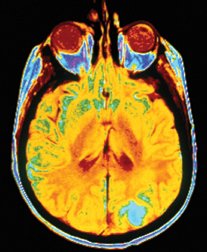

News Humans Nobel prizes go to scientists harnessing odd phenomena Superconductivity, superfluidity, imaging with magnetism, and membrane chemistry By Nathan Seppa, Peter Weiss and Kate Ramsayer October 8, 2003 at 12:07 pm - More than 2 years ago Share this:Share Share via email (Opens in new window) Email Click to share on Facebook (Opens in new window) Facebook Click to share on Reddit (Opens in new window) Reddit Click to share on X (Opens in new window) X Click to print (Opens in new window) Print The 2003 Nobel prizes in the sciences were announced early this week. A PEEK INSIDE. Magnetic resonance imaging scans, such as this one of the brain, can help physicians diagnose cancer.